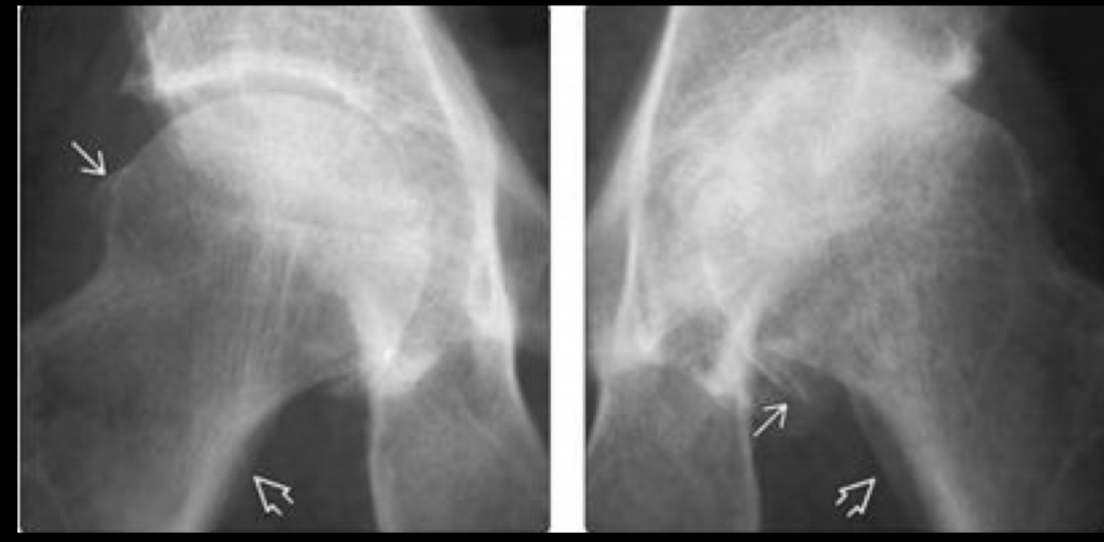

tipos de pinzamiento femoroacetabular

A

• CAM: Deformidad del cuello femoral

• Pincer: Sobrecobertura del acetábulo

• Mixto

Rx. que se piden en el pinzamiento femoroacetabular

• Ap y oblicua

• Axial Dunn

No lateral porque se sobreponen las estructuras como en el hombro

Mejor estudio para ver el pinzamiento femoroacetabular y qué se ve

RM

- Permite ver edema oseo

- Pinzamiento leve

- Quistes

- lesión del labrum